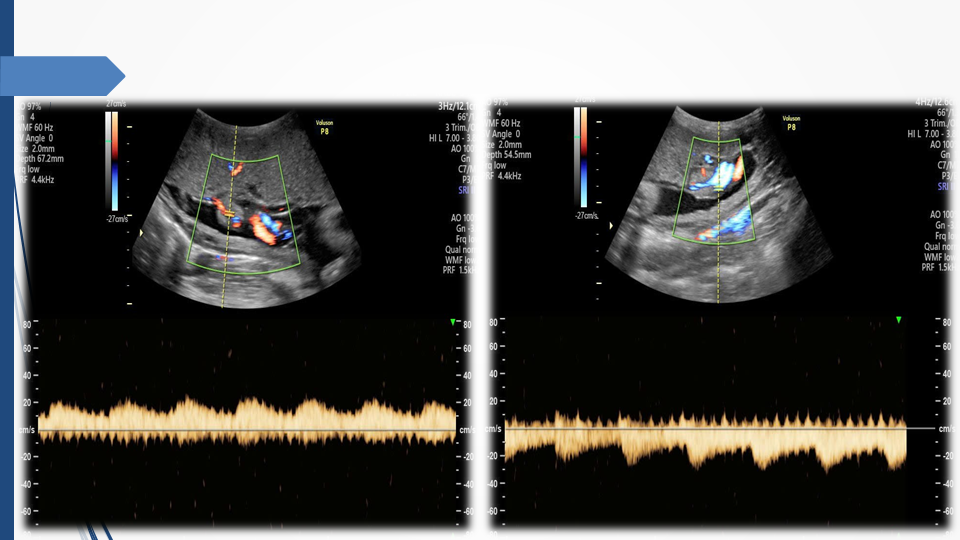

Tầm soát chủ động bất thường dây rốn và tuần hoàn thai để giảm thiểu nguy cơ thai lưu đột ngột - Báo cáo loạt ca hiếm gặp và khuyến nghị thực hành